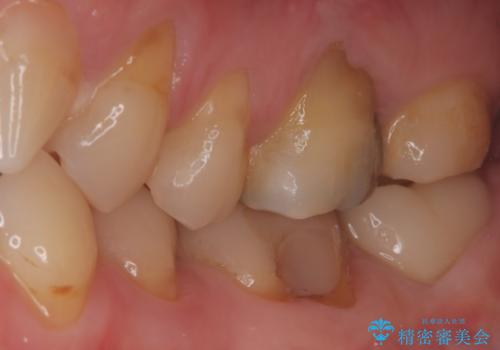

- 患者様は、他院で根管治療を受けたものの、違和感が続くため「しっかりとした治療を受けたい」とのご希望で来院されました。診査の結果、根管内の感染が完全に除去されておらず、根の先に炎症が残っている状態でした。そこで、精密根管治療を行い、感染源を徹底的に除去する計画を立てました。マイクロスコープを使用し、4回の治療で根の内部を清潔にし、最終的にしっかりと密封することで、長期的な安定を目指しました。

治療は、まず根管内の古い充填材を取り除き、感染部分を徹底的に洗浄・消毒することから始めました。ラバーダム防湿を使用し、治療中の細菌感染を防ぎながら、マイクロスコープを用いて根管の細部まで確認しながら処置を進めました。4回の治療で感染の除去と根管の封鎖を行い、最終的に土台を立てて被せ物の準備を整えました。患者様からは「違和感がなくなり、噛んでも痛くない」と喜びの声をいただきました。